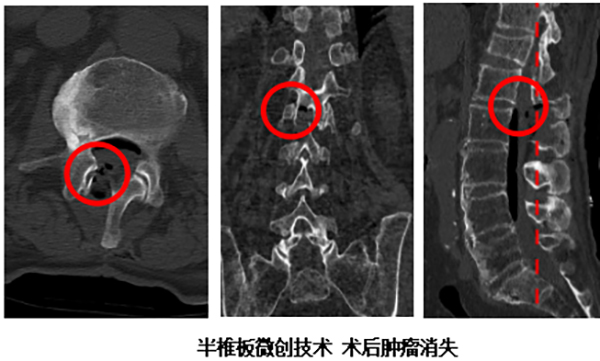

近日,北京怀柔医院神经外科成功诊治了这样一例病例。一位70多岁的患者,长期被慢性腰部疼痛所折磨,且这种疼痛的性质颇为特殊,它不仅局限于腰部,更向身体两侧的肋骨区域放射。这种“不按常理出牌”的疼痛模式引起了患者的警觉,遂前往骨科就诊。经过详细的腰椎核磁共振(MRI)检查,真相浮出水面:导致疼痛的根源并非普通的腰椎间盘突出或腰肌劳损,而是腰椎椎管内长了一个“占位性病变”,也就是我们常说的肿瘤(多为良性),它压迫了支配感觉的神经根,从而引发了奇异的放射痛。

明确诊断后,患者转入神经外科接受进一步治疗。神经外科行政副主任(主持工作)丁小明带领团队对患者病情进行了深入评估,最终决定为其实施手术。与传统手术相比,丁小明团队秉承“精准微创”的现代神经外科理念,创新性地采用了“半椎板入路”手术方式。这意味着医生仅需切除一侧的部分椎板骨质,便能建立一个足够的手术通道,精确抵达并完整切除肿瘤。 这种术式的最大优势在于,极大地保留了对侧椎板及韧带结构的完整性,如同打开一扇“小窗”解决问题,而非拆掉“一整面墙”,从而最大限度地保护了腰椎的力学稳定性,有效避免了术后脊柱失稳、长期腰背痛等传统手术可能带来的并发症。术后,患者恢复迅速,困扰多时的放射性疼痛症状立即显著缓解,取得了立竿见影的治疗效果。